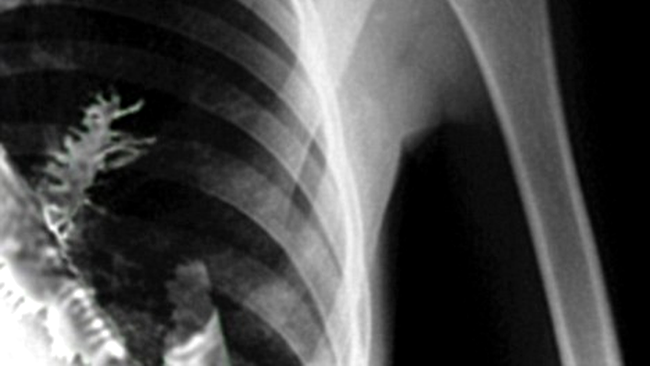

Un barbat in varsta de 28 de ani din orasul Izhevsk, Rusia, a mers in vizita la medic deoarece acuza dureri in piept si tusea expectorand sange. Privind radiografia barbatului medicii au crezut ca acesta are cancer.

Chirurgul Vladimir Kamashev de la Centrul de Boli Canceroase Udmurtian a dorit sa-i faca o biopsie, iar cand au taiat din plaman o bucata de tesut, nu i-a venit sa creada peste ce a dat: un copac (un molid) de cinci cm incoltise acolo.

Medicii care l-au operat pe barbat cred ca acesta a inhalat o samanta care a incoltit in plamanul sau. Capilarele ii erau atinse de copacel, fapt care ii provoca barbatului dureri crunte in piept.